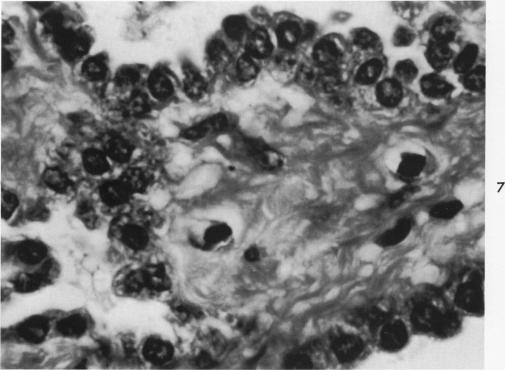

Desquamative interstitial pneumonia. An electron microscopic study.

Am J Pathol. 1970 Sep;60(3):347-70.